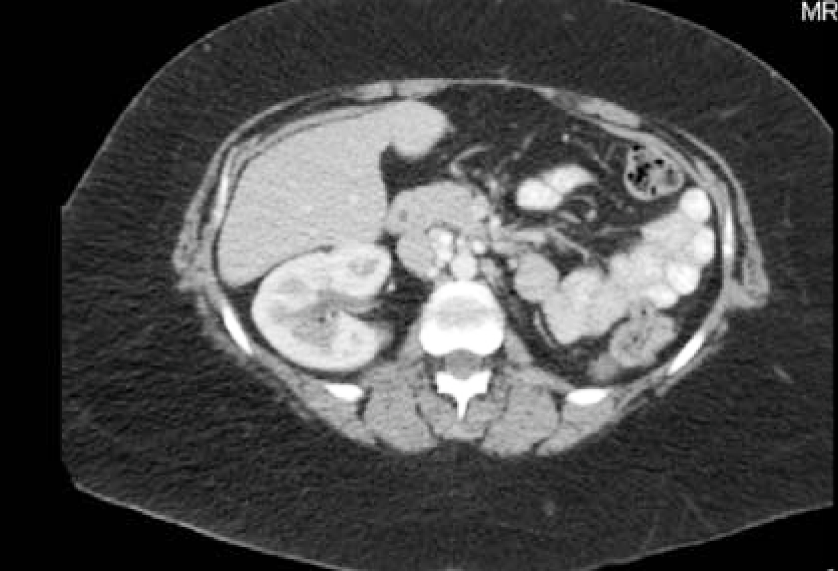

A 55-year-old female with no significant PMH and who had been postmenopausal for five years, presented with the complaint of abdominal pain, bloating, nausea and vomiting that initially occurred three months before admission. Her symptoms started with indigestion, then progressed to nausea, vomiting, bloating and abdominal pain. She presented to an outside hospital, where an obstruction series noted several air fluid levels and haziness suspicious for ascites. A CT abdomen pelvis revealed large ascites, 11x8.7 cm heterogeneous mass displacing the uterus anteriorly and a 7x5.5cm heterogeneous mass in the right adnexa and omental nodularity (Figure 1, 2, and 3). The patient was then referred to a gynecologic oncologist due to suspicion for a gynecologic malignancy and sent to our ER for ongoing abdominal pain, nausea, vomiting and bloating.

Figure 1: CT scan abdomen and pelvis. Splenic implant present.

Figure 2: CT scan abdomen and pelvis. Large ovarian mass.

Figure 3: CT scan abdomen and pelvis. 11 x 8.7cm heterogeneous mass displacing the uterus anteriorly.